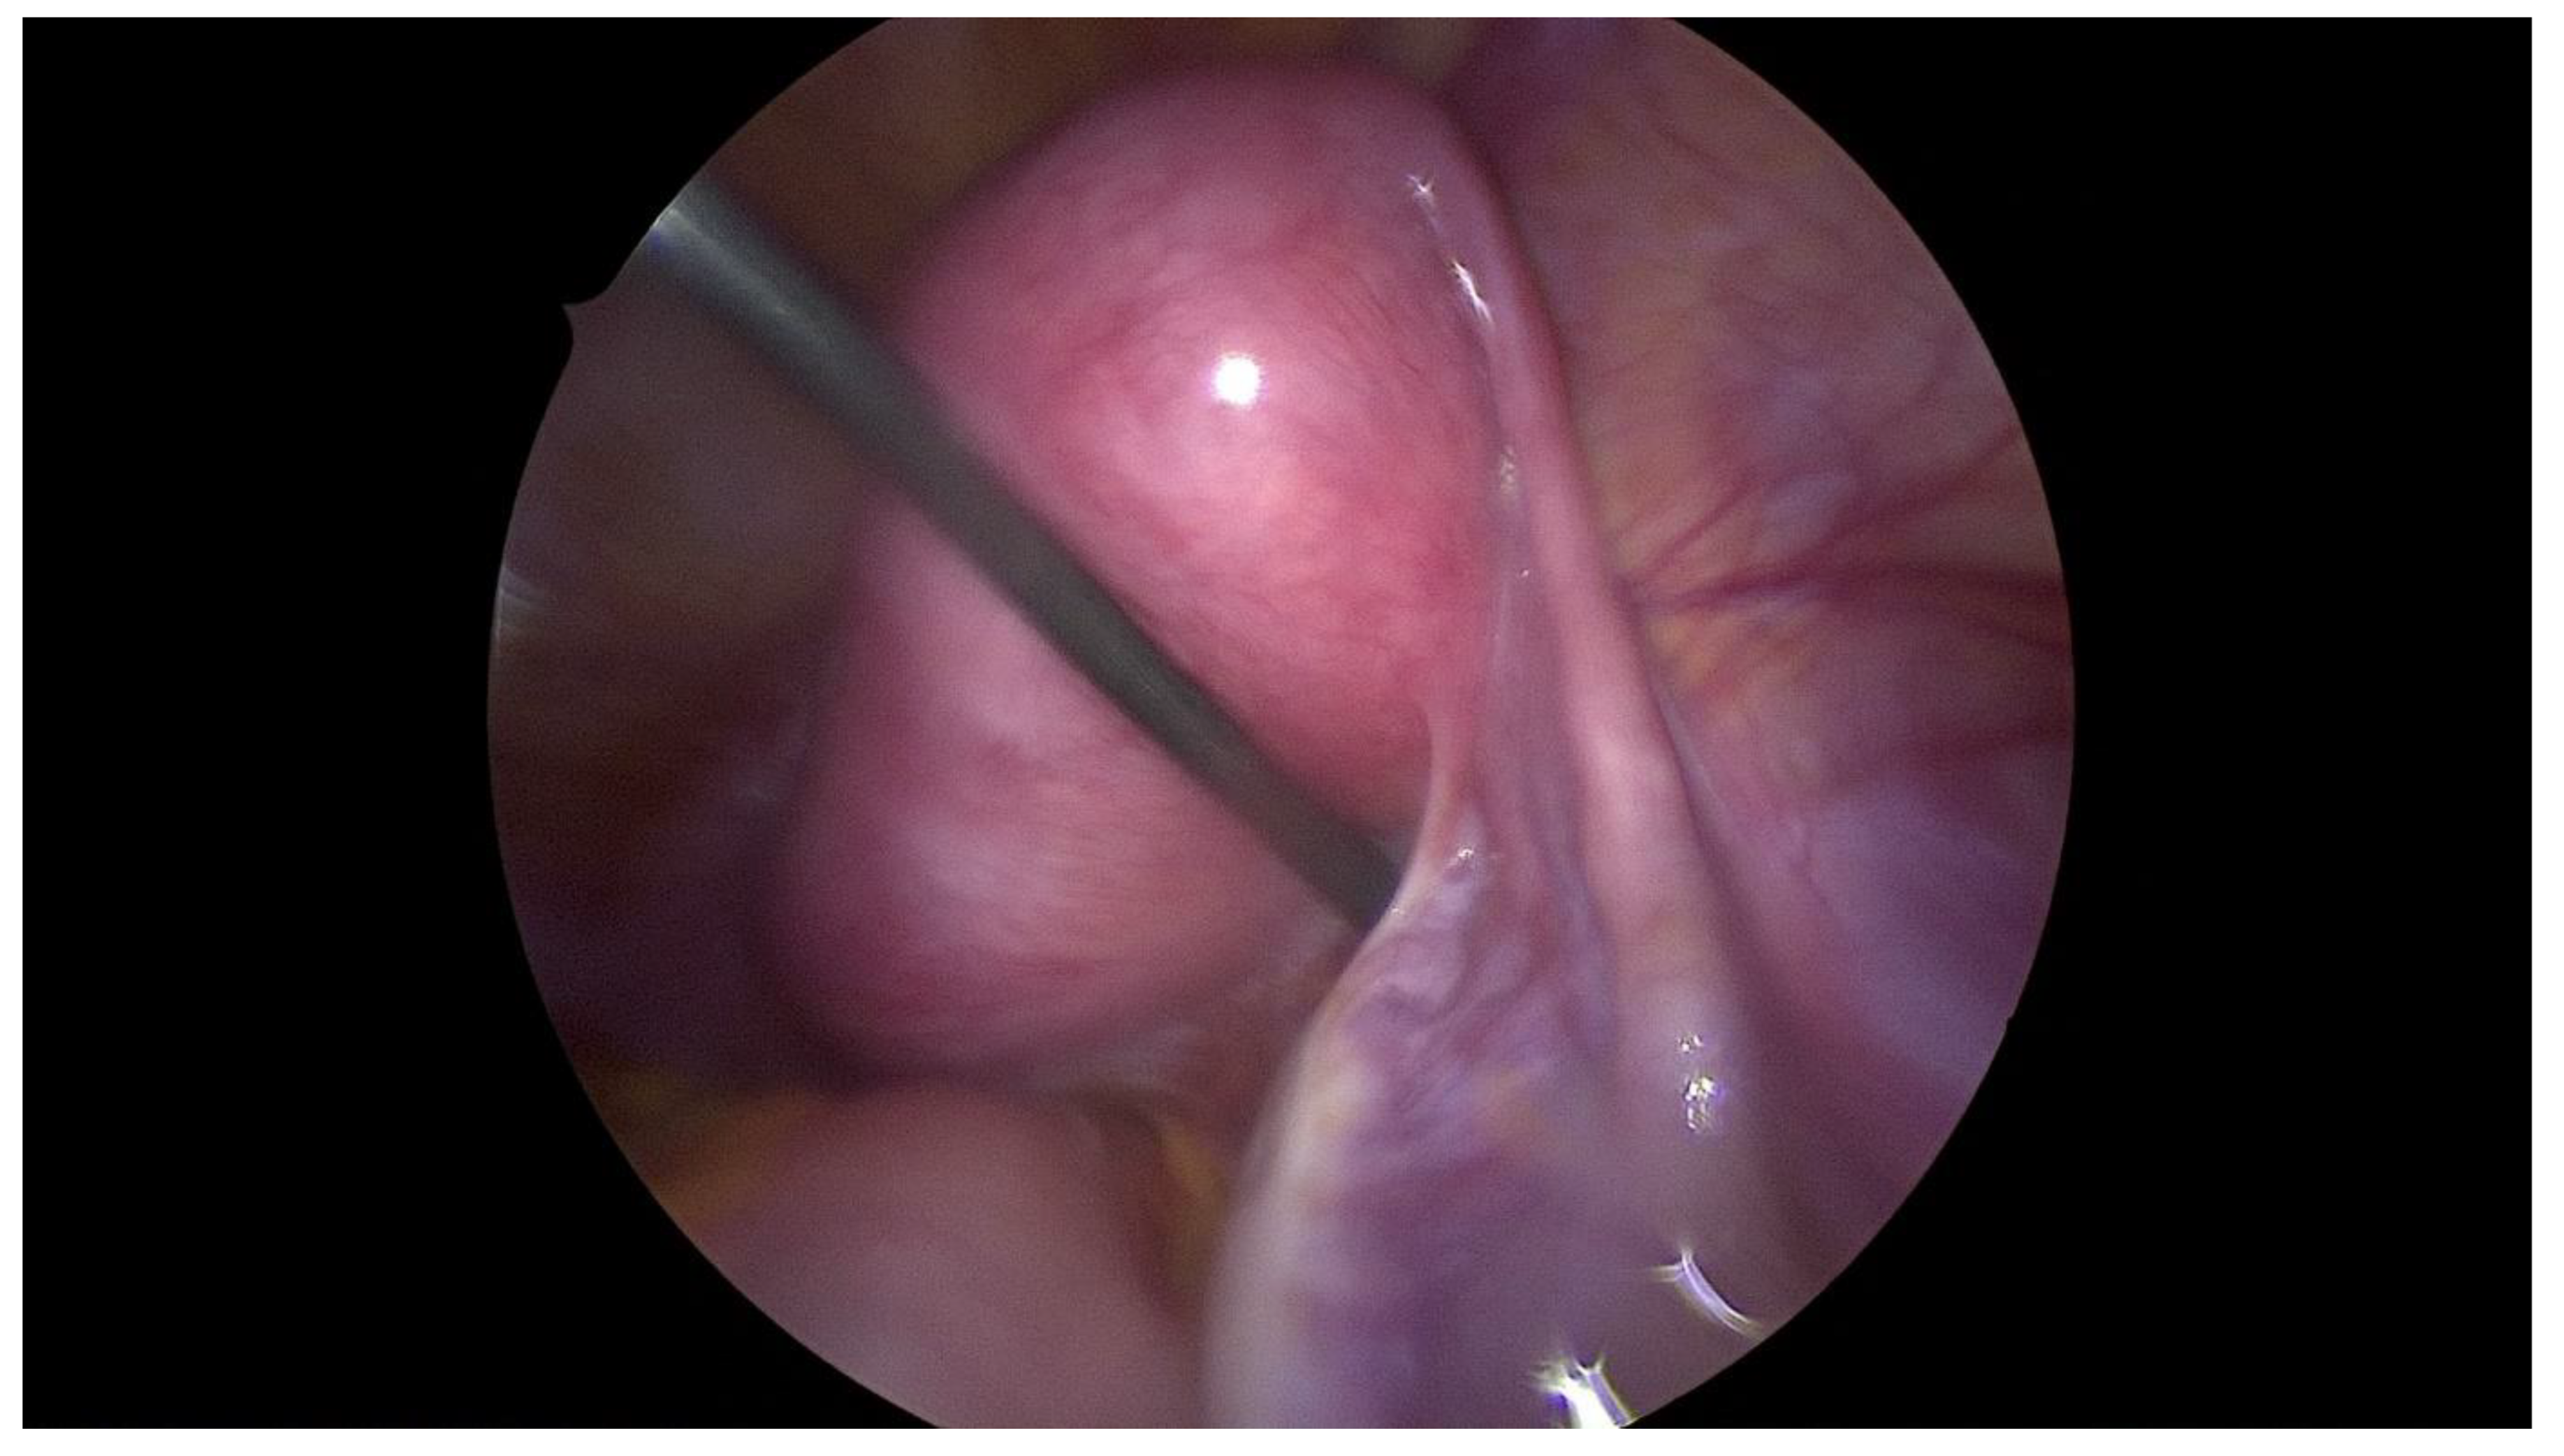

Step 3 Surgical management Surgery is necessary when acute abdominal symptoms are present. “Wait and see” approach is only possible when the clinical situation allows it. Perform laparoscopy and vaginoscopy in order to achieve the correct diagnosis and treat concomitant hematosalpinx and endometriosis [14]. Intraoperative US is helpful to evaluate the place of resection. Unnecessary lengthening the time to diagnosis, contributes to unindentent consequence. |

Step 4 Postoperative management The insertion of uterine catheter filled with saline into a place of stenosis allow to avoid the risk of possible restenosis [15]. Continuous oral contraceptives are recommended to avoid possible consequences like the risk of restenosis. |